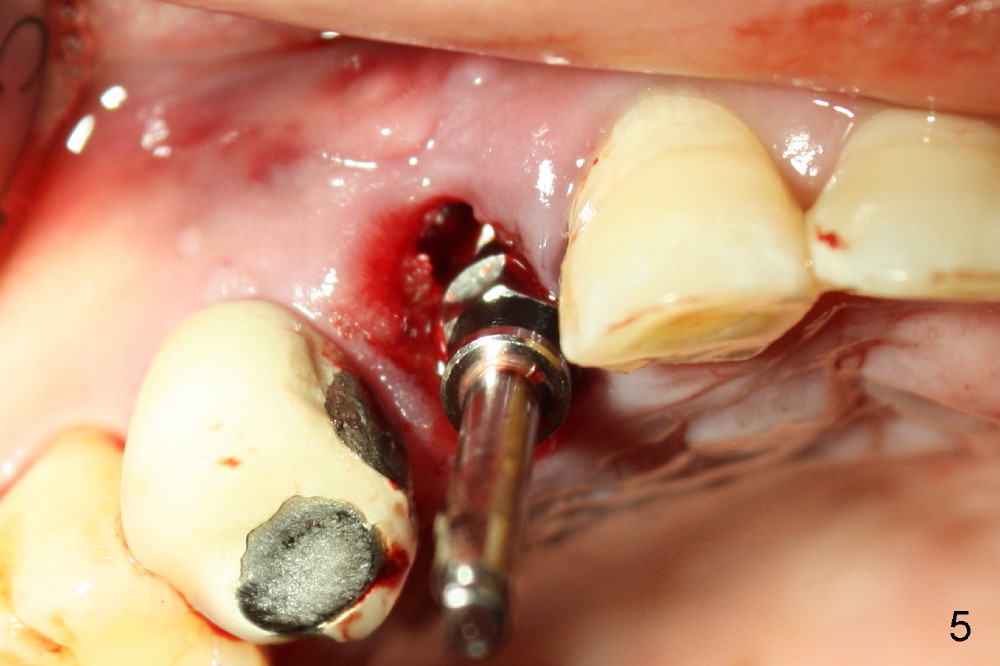

A 57-year-old man refuses treatment for the tooth #5 for 22 months (Fig.1). He suddenly shows up because of severe bleeding from the fistula of the tooth (Fig.2 <). After lengthened discussion, he agrees extraction (Fig.4) and immediate implant (Fig.5-8).

In spite of large periapical radiolucency (Fig.1 *), osteotomy is easier than expected. Use 2 mm pilot drill, 2.5-3.5 mm reamers from 14 mm (bottom of the socket) to 17 mm (sinus floor). The initial point for osteotomy at the bottom of the socket is easy to establish, because it is flat. By the time 5x20 mm tap is inserted, it is palatal (Fig.5). It is mandatory because the buccal plate has been perforated. The tap has to be inserted deeper (from 17 mm to 20 mm, Fig.6) to achieve stability. Insertion torque of 5x20 mm implant (Fig.7 I) is > 60 Ncm. The implant remains palatal so that there is space for bone graft (Fig.8 *). But the bone graft is a little over packed; there is no room to place collagen dressing. The latter will be dislodged and bone graft will be lost if perio dressing is loose prematurely. The perio dressing may have to be re-applied. Depth of bone graft is deemed sufficient if the implant threads are covered. Maximum will be on the rough surface. Physiologically, bone does not extend to the gingival margin.